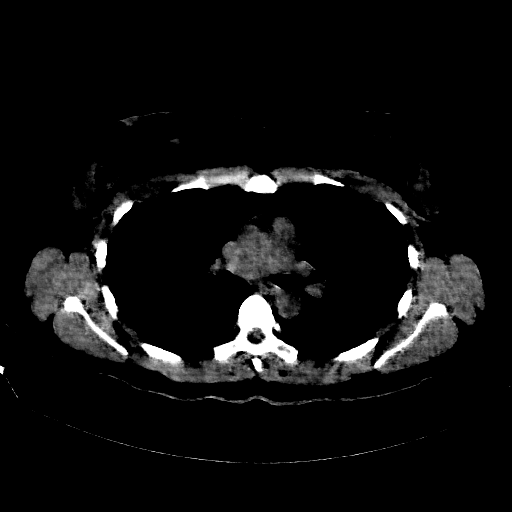

Reconstructed NATIVE CT scan (cycle consistency)

No window - Raw intensity values

Targeted Slice 70 - Lung Window Analysis (Generated vs Real Venous)

0.189

Lung SSIM

717.2

Lung RMSE

662.0

Lung MAE

Average Lung Window Metrics Across All Slices (170 slices) - Generated vs Real Venous

0.174

Lung SSIM (Avg)

707.8

Lung RMSE (Avg)

651.0

Lung MAE (Avg)